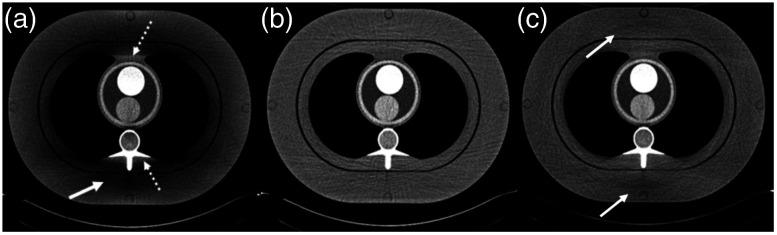

We provide a review of the key computed tomography (CT) technologies developed since the late 1980s and offer an overview of one of the future technologies under development. The focus of this review is mainly on the hardware and system development. The topics on the historical event linked to the early days of CT development and other innovations that contributed to the CT development, such as advanced image reconstruction techniques, are covered by companion papers in this special issue. The review is divided into five major sections, each linked to a key innovation in CT: helical spiral data acquisition, multi-slice CT, wide-cone CT, dual-source CT, and spectral CT. Given the limited scope of this review, only one of the future technologies, photon-counting CT, is discussed in detail. Whenever possible, both theory of operation and clinical examples are provided. Theoretical analyses, phantom results, and clinical examples clearly demonstrate the efficacy and clinical relevancy of five historical technology developments and one future technology in CT. These technologies have improved and will continue to improve CT performance in terms of isotropic volume coverage, improved temporal resolution, and material differentiation and characterization capabilities. Over the past 30 years, technological developments of CT have contributed to the success of CT in many clinical applications such as trauma, oncology, cardiac imaging, and stroke. Advanced clinical applications have and will continue to demand more advanced technology development.

我们回顾了自20世纪80年代末以来开发的关键计算机断层扫描(CT)技术,并概述了一种正在开发的未来技术。本综述的重点主要是硬件和系统开发。与CT早期发展相关的历史事件以及其他有助于CT发展的创新,如先进的图像重建技术等主题,在本期特刊的相关论文中有所涵盖。本综述分为五个主要部分,每个部分都与CT的一项关键创新相关:螺旋数据采集、多层CT、宽锥CT、双源CT和光谱CT。鉴于本综述的范围有限,仅详细讨论了一种未来技术——光子计数CT。只要有可能,都会提供操作原理和临床实例。理论分析、模型结果和临床实例清楚地证明了CT的五项历史技术发展和一项未来技术的有效性和临床相关性。这些技术已经并将继续在各向同性容积覆盖、提高时间分辨率以及物质区分和表征能力方面改善CT性能。在过去30年里,CT的技术发展推动了CT在创伤、肿瘤学、心脏成像和中风等许多临床应用中的成功。先进的临床应用已经并将继续需要更先进的技术发展。